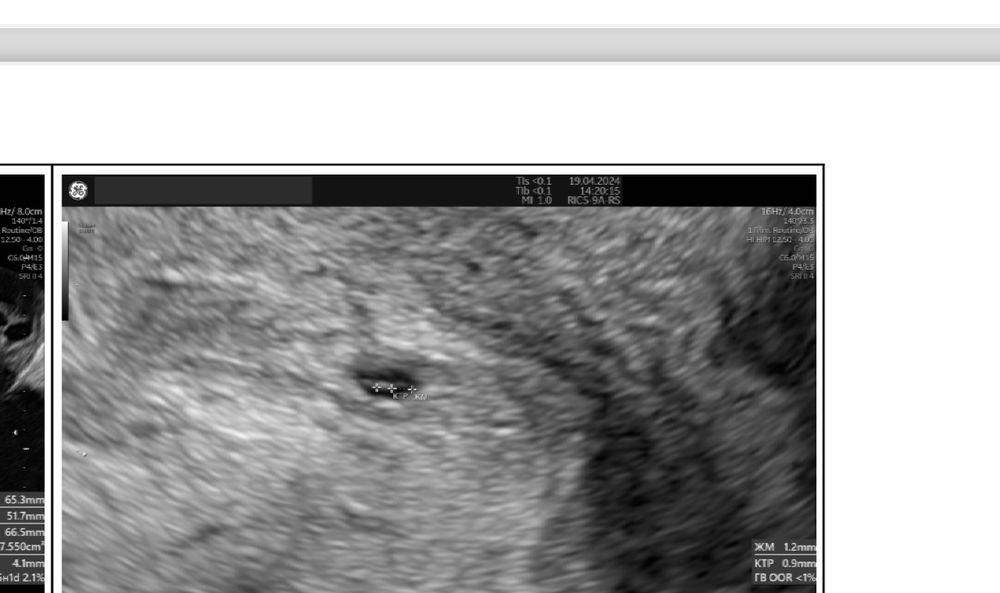

Я конечно до сих пор не могу понять как так получилось…Неделю назад нашли плодное яйцо в матке ,где уже был и желточный мешок и ктр…Вчера утром начались резкие боли до потери сознания..Сразу же на скорой отправили в больницу ,сделали узи и экстренно прооперировали..Лопнула труба,началось внутреннее кровотечение ,на момент операции давление было 70/40, и я потеряла более двух литров крови ..Сейчас в реанимации ((Ну как так ,а как же прошлое узи (((

Мама ангелочка и дочек, кровотечения из матки не было . Я спрашивала после операции, мне матку не чистили .Перед операцией когда делали узи,там вся брюшная полость была в крови ,ничего не было видно